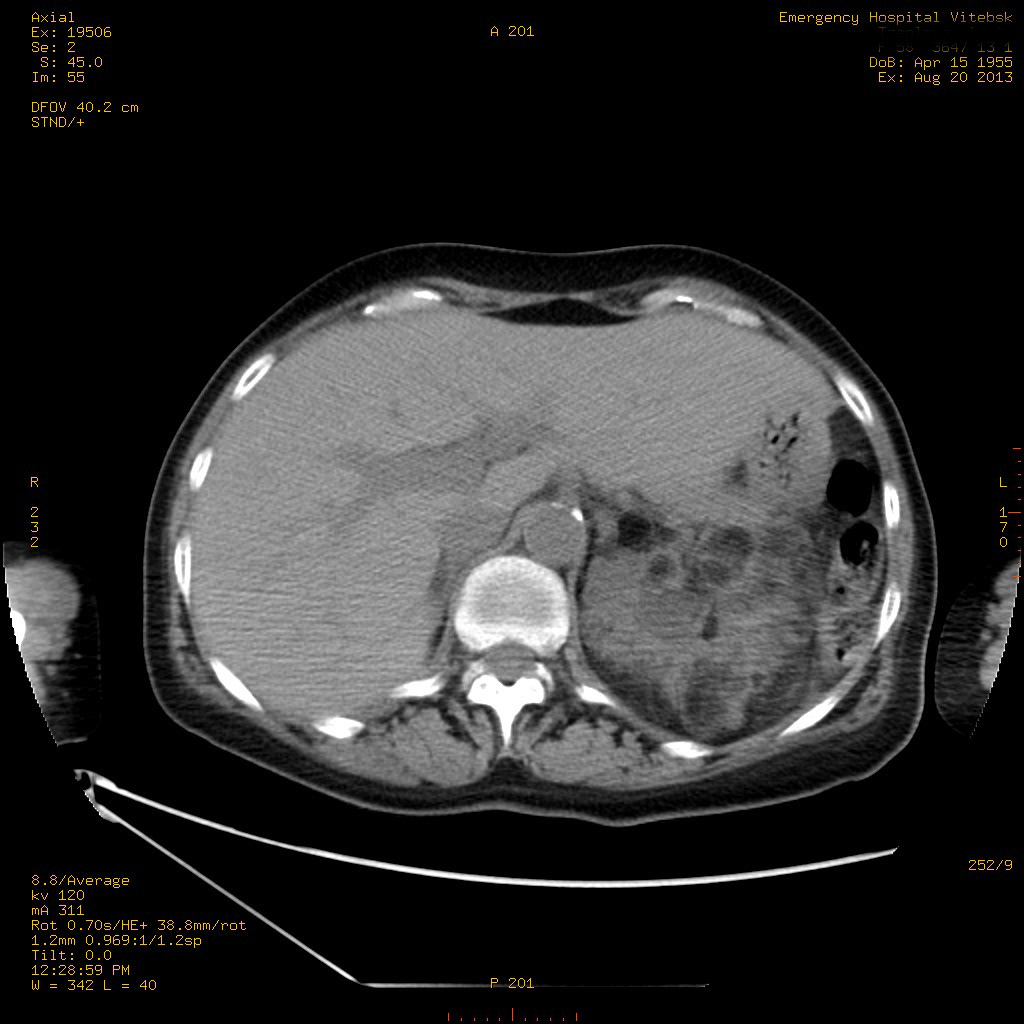

УЗИ почек - туберозный склероз

Пожилая женщина с нормальными мочевиной и креатинином.

Ангиомиолипоматоз почек , думаю компонент туберозного склероза.

Да, туберозный склероз.

Случай консультирован на кафедре радиологии Католического университета г.Лёвен (Бельгия) - зав каф. профессор Р.Оуен.